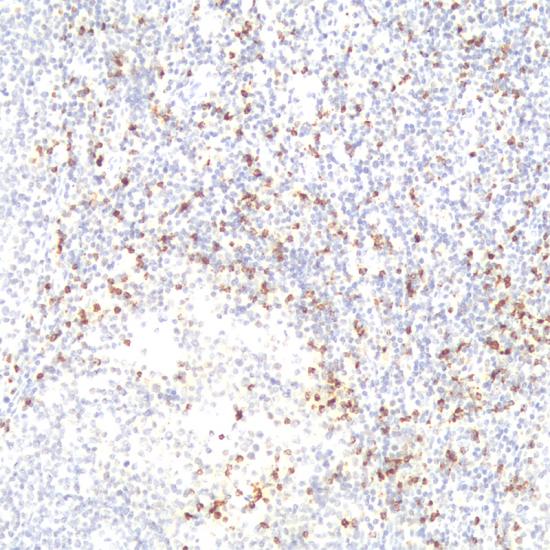

TIA-1

TIA-1抗體試劑(免疫組織化學(xué)) 閩廈械備20180274號

• 預(yù)處理:

熱修復(fù)

• 陽性部位:

細(xì)胞漿

• 陽性對照:

扁桃體

• 適用組織:

石蠟

• 免疫顯色試劑:

iVision?

• 產(chǎn)品編號:

AM0226

• 種屬來源:

鼠單抗

• 克隆號:

2G9A10F5

• 手工規(guī)格/ML:

1、3、6、0.2(濃縮液)

• 儀器規(guī)格/人份:

30、60、120

此抗體所識別的抗原位于具有細(xì)胞溶解能力的一類淋巴細(xì)胞內(nèi)。研究表明,TIA-1在T細(xì)胞或NK細(xì)胞來源的腫瘤表達(dá)陽性,如60%~70%退行性大細(xì)胞淋巴瘤、大多數(shù)的大顆粒淋巴細(xì)胞白血病等表達(dá)陽性,而所有B細(xì)胞來源的淋巴瘤陰性表達(dá)。此抗體主要用于T細(xì)胞淋巴瘤和NK細(xì)胞淋巴瘤的診斷。